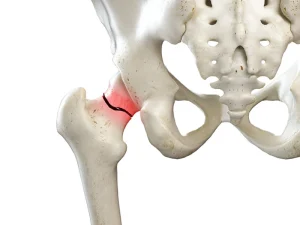

شکستگی لگن یکی از مهلک ترین شکستگیهای بدن انسان است. این نوع شکستگی نه تنها استخوان بدن، بلکه کل بدن و عملکرد آن را تحت